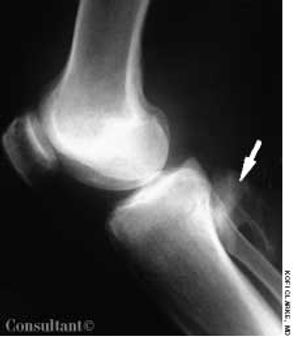

A 44-year-old man with a history of grand mal seizures experienced knee pain while walking. The pain was more severe in the left than in the right knee. The patient had a history of trauma to his left knee caused by falling during seizures.